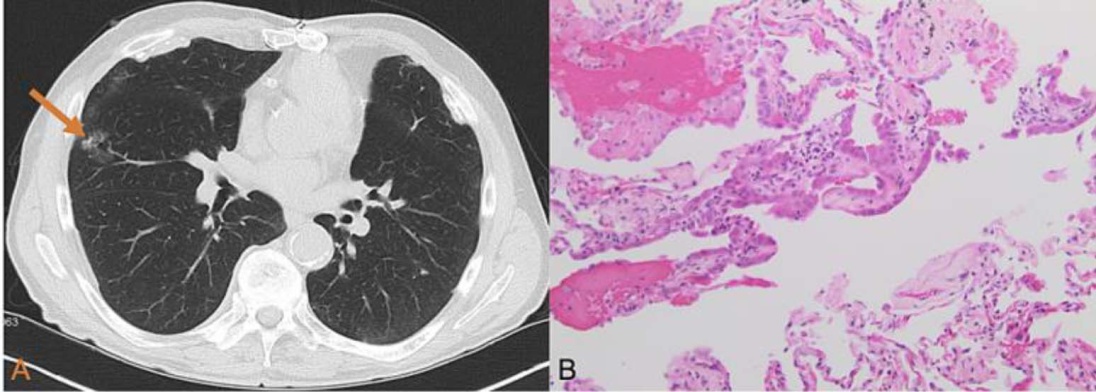

肺腺癌的发展是一个持续的过程,目前主要认为其源于不典型腺瘤样增生,不典型腺瘤样增生常较局限,以肺泡II型细胞和/或Clara细胞增生为特点,衬覆于肺泡壁大体上,细胞间存有空隙且不延续,结节直径常 ≤ 5 mm (见图1);之后发展为原位腺癌,肿瘤细胞继续沿肺泡壁生长,肺泡腔无聚集,无间质、血管及邻近胸膜浸润(见图2);若此时不予干预,放任肿瘤继续生长则有可能微浸润腺癌,直径多 < 3 cm,表现为贴壁生长的孤立结节,伴有1处或多处 < 5 mm浸润灶,大多数微浸润腺癌为非黏液性(见图3);微浸润腺癌再往下发展即是浸润性腺癌[27]。大体标本上,浸润性腺癌多表现为界限不清的灰黄色外周型病变,可为单发或多发。部分肿瘤分泌大量黏蛋白,呈胶冻状或蛋白样外观,空洞形成较为少见。约65%的腺癌位于肺周边,常邻近脏层胸膜,可引起胸膜纤维化或皱缩。少数周围型腺癌可播散至胸膜间隙,广泛覆盖脏层与壁层胸膜,形态类似弥漫性间皮瘤极少数腺癌表现为支气管内息肉样肿块[28]。需要注意,贴壁型生长模式并非肺原发性腺癌特有,亦可见于转移性肿瘤(如来自乳腺或甲状腺),这些肿瘤TTF-1也可能呈阳性。利用肺腺癌这些组织生长的特点,人为进行病理分级,为临床提供肿瘤分期,把握治疗时机,并对治疗方案效果做正确的评估具有重要作用。

Figure 1. Atypical tumor-like hyperplasia of the lung

1. 肺不典型瘤样增生

Figure 2. Lung adenocarcinoma in situ

2. 肺原位腺癌

Figure 3. Pulmonary minimally invasive adenocarcinoma and pulmonary adenocarcinoma in situ

3. 肺微浸润腺癌

图1(A)显示右中叶有一个2.8 cm的磨玻璃样结节(橙色箭头所示)。未发现纵隔淋巴结肿大迹象。图1(B)显示可见肺实质一个边界清晰的肺泡腔区域,其内衬有细胞体积增大、核明显增大的区域以及轻度核多形性。图2(A)~(C)显示一种持续存在的云雾状阴影,病理切片如图2(D)所示,镜下可见立方形、相对均匀的肿瘤细胞群体覆盖增厚及保存完好的肺泡壁。图3影像显示右肺上叶发现了一个孤立的磨玻璃样阴影结节。病理切片显示病变主要由鳞状肿瘤生长组成,伴有几个厚度小于5毫米的侵袭性腺泡成分(箭头所示)。注:以上图片来源于参考文献[38]-[40]